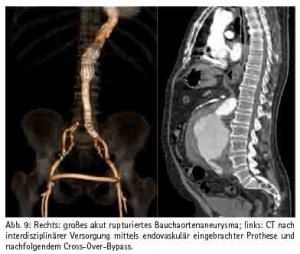

Wie in vielen medizinischen Fächern ist die Entwicklung in der Gefäßmedizin gekennzeichnet durch eine Zunahme der interdisziplinären Schnittstellen, die u. a. bedingt ist durch den Fortschritt der endovaskulären Verfahren. So ist heute nahezu jedes arterielle Stromgebiet für den interventionell tätigen Gefäßmediziner zugänglich. Die Ergebnisse sind dabei in einigen Indikationsbereichen von einer guten Qualität, so dass inzwischen z. B. für die descendierende Aorta der endovaskulären Therapie der Vorzug gegeben wird (Abb. 9). Für die Revaskularisation der Arteria carotis (Abb. 10), der Bein-Beckenachse (Abb. 11) und der Behandlung des Bauchaortenaneurysmas existieren sowohl interventionelle als auch chirurgische Verfahren, die nicht als konkurrierend, sondern als sich ergänzend zu verstehen sind. So sind konservative, interventionelle und chirurgische Disziplinen mittlerweile nicht nur voneinander abhängig, sondern auch zusammengewachsen. Das Bild mehrerer Gefäßdisziplinen, die gleichzeitig am Patienten eine Therapie durchführen, gehört zunehmend zum klinischen Alltag. Die optimale Therapieauswahl wird dabei interdisziplinär im heart- bzw. vascular team abgesprochen. Daher sind die Bestrebungen in Richtung eines Organzentrums nur konsequent.

Als beispielhaft sei die endovaskuläre Ausschaltung des Bauchaortenaneurysmas genannt. Hierbei wird unter Röntgenkontrolle über die Leistenarterien eine Stentprothese in die Bauchaorta vorgeschoben und somit das Aneurysma ausgeschaltet. Dies wird mittlerweile auch im Rupturstadium durchgeführt, wobei nach Aneurysmaausschaltung ein cross over Bypass zusätzlich notwendig ist. Der Eingriff erfolgt in der sog. Angiosuite sowohl durch Radiologen als auch durch Gefäßchirurgen. Ebenso können Mehretagenläsionen an der Becken-Bein Achse durch chirurgische und gleichzeitig interventionelle Katheterverfahren revaskularisiert werden.